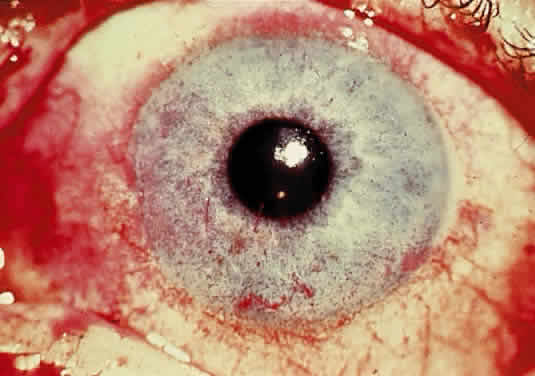

OCULAR FINDINGS. The outstanding clinical feature common to all three phenotypes is the corneal and conjunctival cystine crystal deposition (Figs. 3 and 4). Photophobia is often the only presenting visual symptom; this may be incapacitating and associated with blepharospasm.

Corneal deposits appear as a layer of homogeneously distributed, fusiform or needle-shaped, iridescent crystals situated in the stroma beneath the epithelium. In the infantile form, anterior crystal deposition begins early in life (between 6 and 15 months of age) and proceeds posteriorly as the patient ages; deposition advances more rapidly in the periphery. The anterior location of the crystals may be associated with recurrent erosions.33 The depth of the stromal deposition and the density of crystals is always greater peripherally than centrally. More and larger crystals occur in the superficial stroma. No visual impairment occurs at this early stage. By the age of 7 years, most patients have crystals, either within or on the endothelial surface34,35; markedly decreased corneal sensitivity is also present.36 The spherical contrast sensitivity function is significantly lower in infantile cystinosis than in age-matched controls.37

The conjunctiva has a ground-glass appearance. Polychromatic, polymorphic, rectangular, or rhomboidal crystals can be seen with the biomicroscope.

The uvea contains an abundance of polymorphous crystals. Clinically, these can be seen as glistening dots on the surface of the iris. Thickened iris stroma and posterior synechiae may occur; pupillary block glaucoma38 also has been reported. The entire uvea has polymorphic crystal deposition, most heavily in the choroid. The sclera also has crystal deposition.

The retinal abnormality consists of a generalized depigmentation that may assume a patchy pattern. At first the pigmentary disturbance tends to be peripheral, but it progresses with age. Macular abnormalities have been observed.39 Intracellular crystals also have been seen in the retinal pigment epithelial cells during electron microscopy.